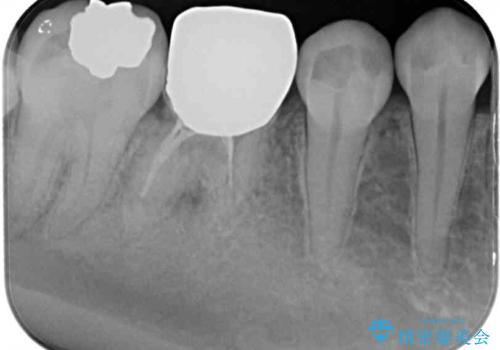

- 近医で奥歯の抜歯が必要であると指摘され、インプラント治療を希望して来院された患者様です。

診察の結果、歯が破折しており抜歯が必要でした。

抜歯後にはストローマンSLActiveを埋入し、補綴治療を行うこととしました。